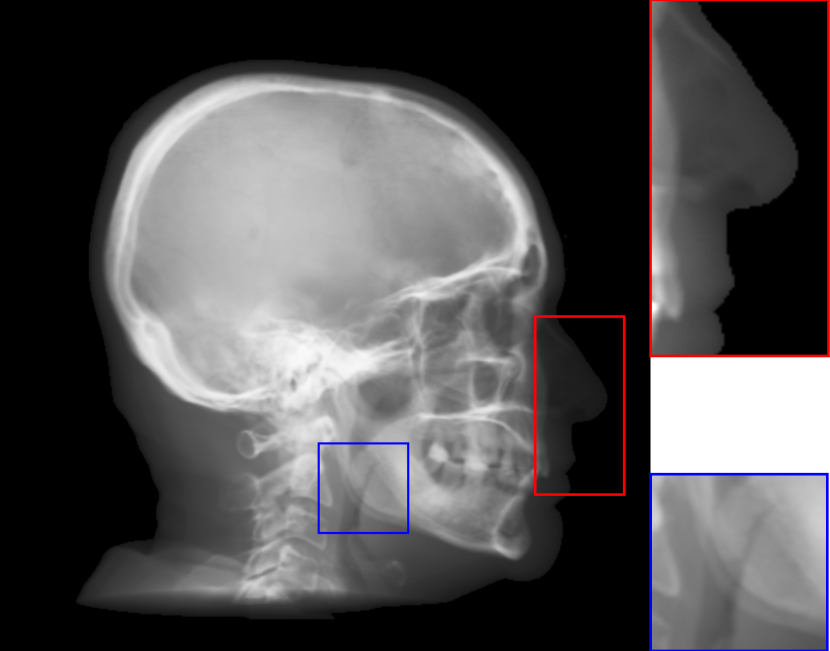

Fig. 8: Synthetic cephalogram examples from 3D CBCT volumes with different methods. (a)-(d) are comparison results while (e)-(h) are the (intermediate) results of our proposed method: (a) RayCast using orthogonal projection; (b) RayCast using perspective projection; (c) MIP using the largest 100 pixels along each orthogonal ray; (d) CycleGAN using patches from (a) and ISBI real conventional cephalograms; (e) RayCast using orthogonal projection from the skeleton enhanced volume; (f) original sigmoid transform of (e) using Eqn. (4) with air background recovery; (g) modified sigmoid transform of (e) using Eqn. (6), the final Type I synthetic cephalogram using orthogonal projection; (h) the final Type I synthetic cephalogram using perspective projection. The nose ROIs are redisplayed in the intensity window [0, 125] for better visualization. The mandible angle ROIs are for the visualization of the difference between orthogonal projection and perspective projection. The perceptual index of each synthetic cephalogram is displayed in the corresponding subcaption.

The synthetic cephalograms generated by different methods are displayed in Fig. 8. Figs. 8(a) and (b) show the cephalograms synthesized by the orthogonal [33] and perspective [21] RayCast methods, respectively, which are the most widely used methods for cephalogram synthesis from CBCT volumes. Comparing Fig. 8(b) to Fig. 8(a), due to different magnification factors of structures at different positions in perspective projection, anatomical structures on both sides of the midsaggital plane cannot overlap well, for example, the projections of the left and right mandible (gonial) angles in the zoom-in ROI in Fig. 8(b). In Figs. 8(a) and (b), the skeleton structures, soft tissues and airways are well observed. However, the image contrast in these two synthetic cephalograms are different from conventional cephalograms (Fig. 2(a)). The cephalogram synthesized by MIP using the largest 100 pixels along each orthogonal ray is displayed in Fig. 8(c). In this subfigure, skeleton structures are well observed since they have high intensity. Nevertheless, low intensity structures, e.g. the throat airway, might disappear. The CycleGAN [59] synthetic cephalogram is shown in Fig. 8(d). Compared with the conventional cephalogram example in Fig. 2(a), it has the closest image contrast. Hence, it achieves the best perceptual index of 5.53. However, some detailed anatomical structures are incorrect. For example, the nose has extremely low intensity in the zoom-in ROI. It also suffers from geometric distortion. As a consequence, the stitching artifacts are visible.

Figure 8(e)-(g) are the Type I synthetic cephalograms of different steps using orthogonal projection. Fig. 8(e) is the orthogonal RayCast celphalogram synthesized from the enhanced CBCT volume using Eqn. (1). Compared with Fig. 8(a), skeleton structures in Fig. 8(e) have higher contrast. Fig. 8(f) is obtained by applying the original sigmoid transform in Eqn. (4) to Fig. 8(e), where the skeleton structures are further enhanced. Moreover, the appearance of Fig. 8(f) is very close to conventional cephalograms. However, the soft tissues like the nose and lips have an almost constant intensity value, as displayed in the zoom-in ROI in Fig 8(f). The final Type I synthetic cephalogram with orthogonal projection is displayed in Fig. 8(g). With the proposed modified sigmoid transform in Eqn. (6), the contrast in the soft tissues is brought back, as displayed in the zoom-in ROI. For comparison, the final Type I synthetic cephalogram with perspective projection is displayed in Fig. 8(h). Compared with Fig. 8(g), the mandible angles in the zoom-in ROI of Fig. 8(h) are not overlapped well due to perspective magnification.